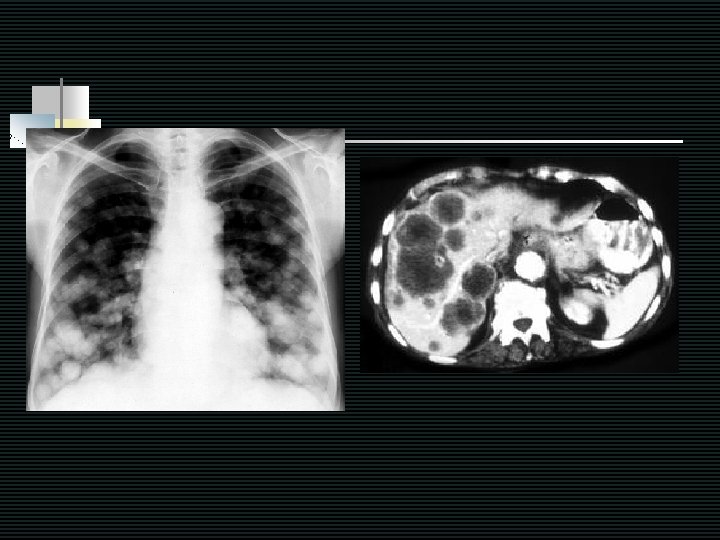

Bone metastasis : Approach 1. Suspected non-hematologic malignancy n Hx & PE - Cough, dyspnea, tightness - GI symptoms - Abdominal mass - Supraclavicular LN - Breast exam - Hematuria n Investigations - ALP ( ) - CXR - PSA (all men) - Mammo (women) - CT chest & abdomen

Take home messages for bone metastasis of unknown primary n n n 1. All men 2. All women 3. All patient - Normal ALP - ALP : PSA : breast PE, mammogram : CXR, ALP, Ca, CBC Rouleaux, Globulin, Cr, Urine bence : solid tumors : if PSA normal, breast and CXR no clue CT chest and whole abdomen